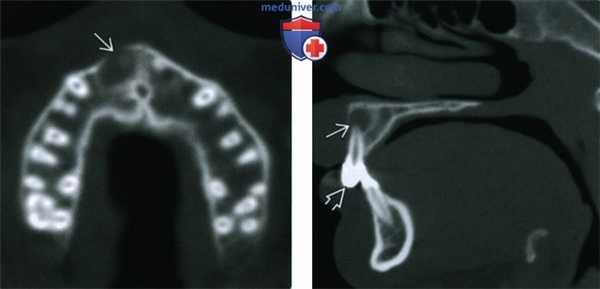

(Слева) При аксиальной КТ в костном окне визуализируется мелкая периапикальная радикулярная киста возле корня центрального резца верхней челюсти справа. Признаков периостальной реакции или наличия объемного образования в мягких тканях за пределами челюсти не определяется.

(Справа) При сагиттальной КТ у этого же пациента визуализируется периапикальная киста и стоматологическая амальгама в этом же зубе.

(Слева) При сагиттальной КТ в коаном окне в области апикального отверстия корня первого премоляра нижней челюсти справа визуализируется однокамерная киста, хорошо отграниченная от окружающих тканей кортикальной пластинкой. Киста тесно прилежит к твердой пластинке и пространаву периодонтальной связки, что свидетельствует о ее воспалительной природе.

(Справа) При сагиттальной КТ в костном окне в верхней челюсти визуализируется периапикальная киста среднего размера, целостность ее верхней стенки на ограниченном участке нарушена. Определяются также признаки ассоциированного с кистой верхнечелюстного синусита одонтогенного характера.